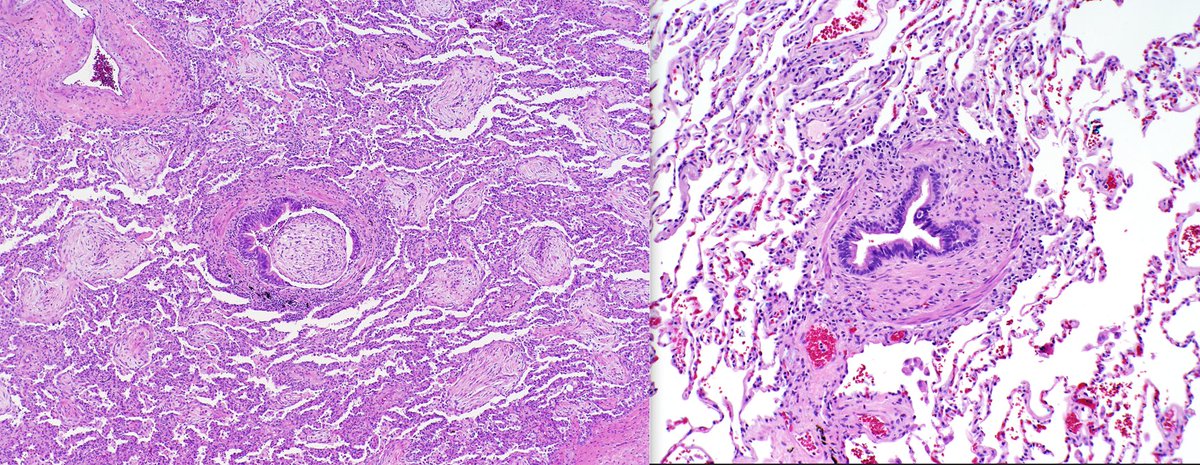

Lung injury patterns which often get confused with each other. Can you name these patterns? Differential? Kamran Mirza MD PhD - کامران مرزا Xiaoyin "Sara" Jiang, MD (She/Her)